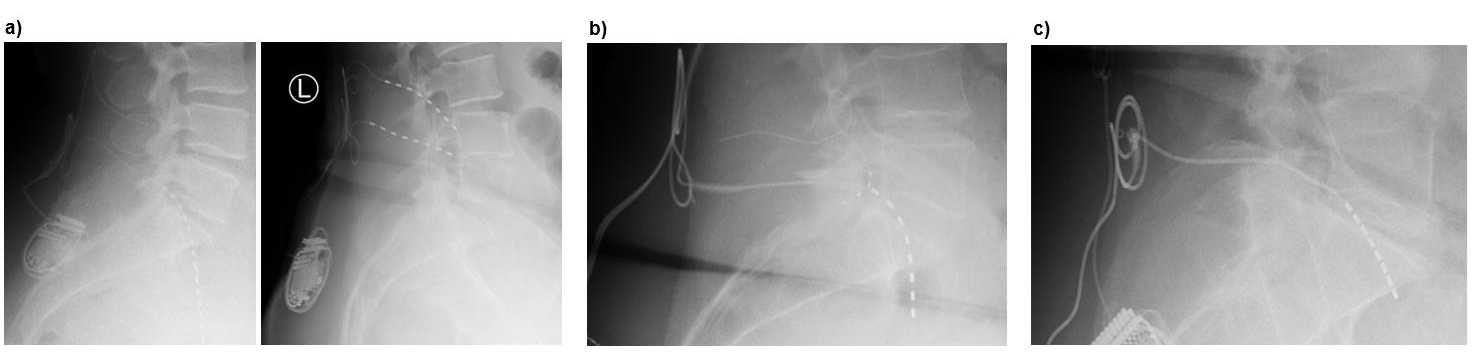

This phenomenon appears to be mechanically induced. The anchoring technique introduces tension vectors that pull the lead toward the skin, particularly when the fascia is tight or the anchor is misaligned with the lead’s natural trajectory. During revision procedures, it was noted that the leads were firmly attached to the anchors, and the anchors were securely fixed to the fascia, thus ruling out improper anchoring technique as the primary cause. In most cases, lateral fluoroscopy or postoperative X-rays revealed the formation of a loop beneath the fascia, indicating progressive extrusion of the electrode (Figure 5a).

Importantly, not all migrated leads required revision. In several cases, the leads remained sufficiently close to the spinal nerve to allow for successful reprogramming. In mild displacements, often involving only a few centimeters, clinical function could be restored by activating more distal contacts (Figure 5a, left).

Fine-tuning anchoring techniques to prevent device related complications: Lead migration remains one of the most significant complications when using the Xtra4 approach. Historically, up to 20% migration rates have been reported, leading to reduced therapeutic efficacy and the need for revision surgery (Figure 5a, right).

Most migration cases were associated with anchoring techniques in which the anchor tip was inserted deep into the fascia, while the distal portion was superficially sutured. This configuration introduced tension vectors that, under the influence of muscle movement, gradually pulled the electrode toward the skin. In most cases, loop formation beneath the fascia was visible on lateral fluoroscopy or postoperative imaging (see Figure 5a). Importantly, no cases of distal migration were observed.

Technique 1: Perpendicular in-fascia anchoring using conventional anchors (Kugler approach): In this approach, a standard sleeve-type anchor (regardless of manufacturer) is inserted perpendicularly into the fascia, aligned with the trajectory of the electrode (Figure 5b). A small fascial incision is made at the needle entry site. The Tuohy needle is removed, the anchor is mounted onto the lead, and both are inserted into the fascial opening. The distal end of the anchor is sutured to secure the lead and then directly fixated to the fascia to prevent retrograde movement (see Figure 5b).

Technique 2: Extra-fascial anchoring with modified anchor (Kohr approach): This technique involves slightly modifying a conventional sleeve-type anchor, positioning it outside the fascia directly at the lead entry point. This configuration’s anchor is a mechanical stop to prevent retrograde lead movement (see Figure 5c).

Figure 5. Lead migration and anchoring techniques. (a) Examples of lead migration: left image shows mild migration with formation of a subfascial loop (<1 cm), where reprogramming maintained effective stimulation; right image shows severe migration (>3 cm), in which reprogramming failed to restore coverage, necessitating surgical revision to correct the lead’s position on the nerve. (b) Perpendicular in-fascia anchoring using a conventional anchor (Kugler approach): a sleeve-type anchor is inserted perpendicularly into the fascia at the lead entry point and secured to both the lead and fascia, preventing retrograde migration. (c) Extra-fascial anchoring with modified anchor (Kohr approach): a conventional anchor is longitudinally cut so the lead exits through its midsection rather than the tip, then fixed outside the fascia at the lead entry site. The tip may be secured into the fascia or removed entirely. In both cases, only the lead—not the anchor—forms the 90° bend.